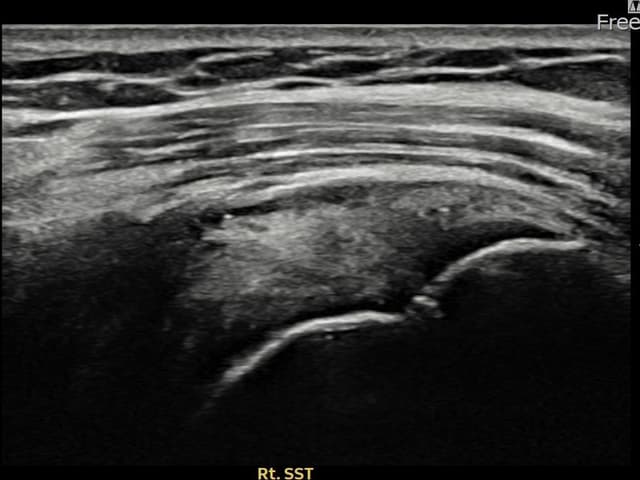

[촬영시기:23.09.01~23.11.03]

[어깨인대 축소봉합술] 우측 어깨 통증이 수개월간 지속되어 내원하셨습니다.